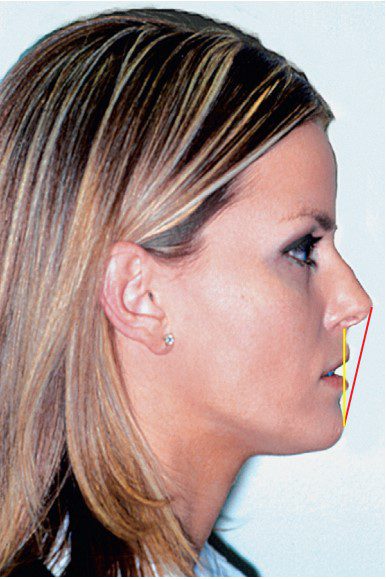

Để xác định mức độ nhô môi, người ta đã sử dụng nhiều mặt phẳng tham chiếu khác nhau. Một trong những mặt phẳng tham chiếu phổ biến nhất trong chỉnh nha lâm sàng là đường E do Ricketts đề xuất, được tạo bởi đường nối từ chóp mũi đến điểm pogonion mô mềm (điểm Pg’).

Hạn chế của đường tham chiếu này là nó bị ảnh hưởng bởi vị trí trước–sau của cằm và mũi. Bất kỳ sai lệch lớn nào về vị trí của cằm hoặc mũi so với chuẩn đều có thể tạo ra ấn tượng sai lệch về vị trí của môi.

Để kiểm soát sự thay đổi của mũi, Burstone đã đề xuất sử dụng đường Sn–Pg’, kéo dài từ điểm dưới mũi (điểm Subnasale – Sn) đến Pg’ (hình 1-25).

Một số tác giả khác sử dụng các góc đo khác, dựa trên các điểm tham chiếu là cằm và môi, không bao gồm mũi, như góc Z, đường S của Steiner, và góc Holdaway.

Góc mũi–môi (nasolabial angle) là một phép đo quan trọng liên quan đến mức độ nhô của môi. Mặc dù góc này cũng bị ảnh hưởng bởi độ nghiêng mũi (mũi hếch lên hoặc cụp xuống), nhưng nó vẫn cung cấp thông tin quan trọng về độ nghiêng của môi trên (hình 1-26).